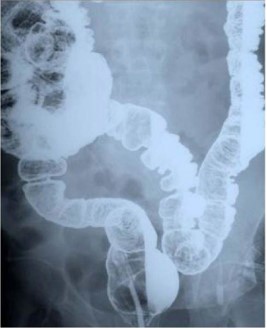

Physical evaluation revealed a middle-aged man who looked healthy, not anaemic and no lymphadenopathy. Abdominal and per rectal examination revealed no abnormal findings and central nervous examination was normal. A barium meal Figure 1 revealed a symptomatic redundant sigmoid colon. A diagnosis of ‘symptomatic redundant sigmoid colon’ grade III [5] was made.

Figure 1: Redundant sigmoid colon (Barium enema X-ray).

Sigmoid colon passed the midline.